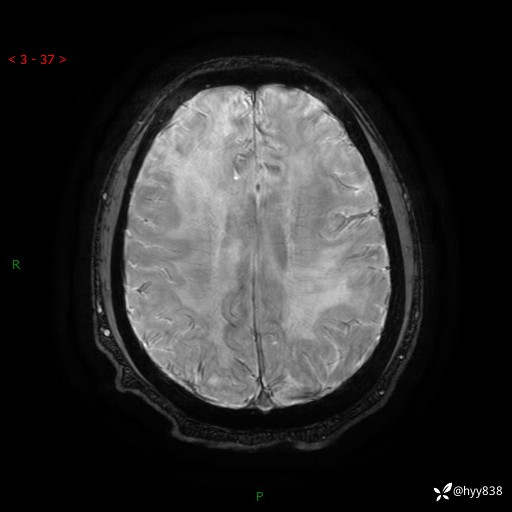

磁敏感成像